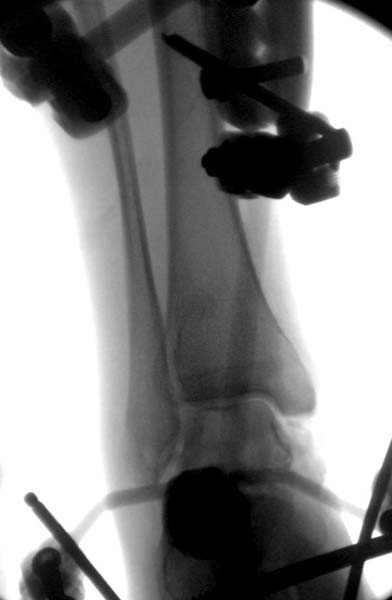

Больная стабильная после хирургических мероприятии и получив добро, приступили к закрытому вправлению таранной кости с укладкой наружного фиксатора. Затем укладка больную на бок и открытый остеосинтез перелома-вывиха головки бедра.

Остеосинтез бедра не стали делать из-за множественных переломов ребер с ушибом грудной клетки и поэтом у закончили фиксацию бедра наружным фиксатором.

Около 11.00 вечера больная переведена в реанимацию, без сознания, но стабильная.. На третьий день провели стабилизацию перелома бедра антеградным остеосинтезом.